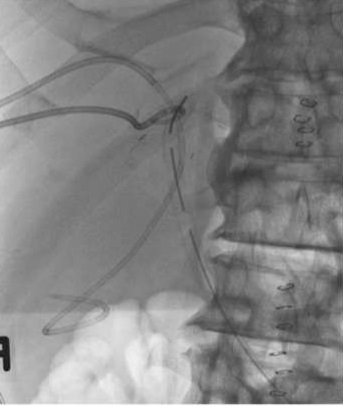

58岁男性 四段肝癌, 左半肝切除术,肝胆管空肠吻合术 术后第七天,肝下引流管持续大量胆汁流出,怀疑胆肠吻合口漏,胆红素正常

58岁男性

四段肝癌,

左半肝切除术,肝胆管空肠吻合术

术后第七天,肝下引流管持续大量胆汁流出,怀疑胆肠吻合口漏,胆红素正常

PTC: Patent HJ anastomosis, no leak

PTC: Obstructed right posterior hepatic duc

PTC: Obstructed right posterior hepatic duct

Biliary drains inserted in RAHD & RPHD Plan: Surgical revision

But: AMI, surgery deferred